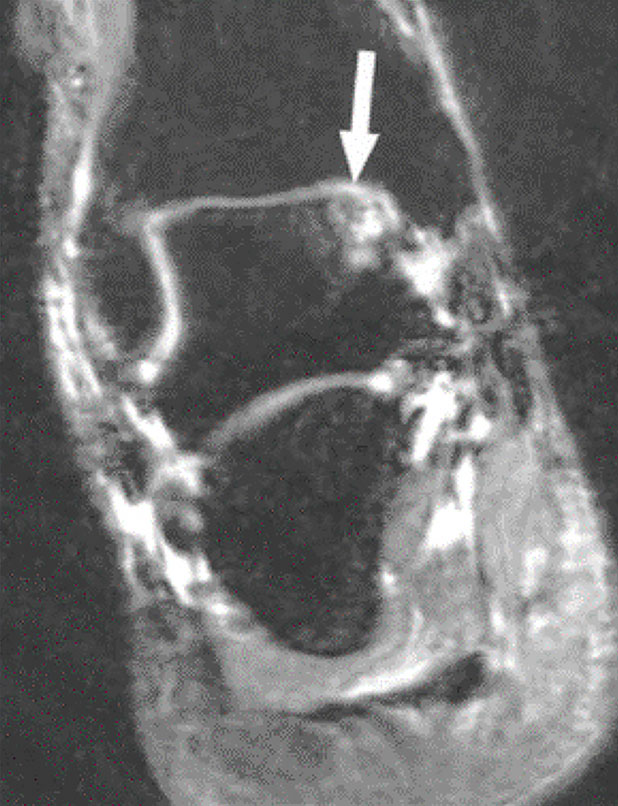

Рис.4.23-4.24 МР-томограммы голеностопного сустава. А — интактная передняя таранно-малоберцовая связка. В — нестабильность голеностопного сустава, связанная с разрывом передней таранно-малоберцовой связки (стрелка).